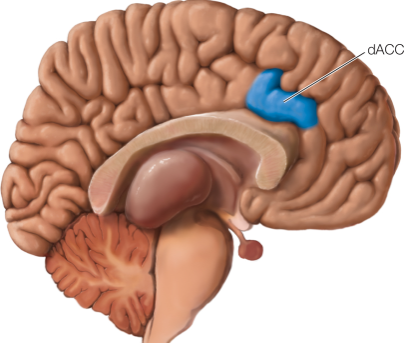

这篇文章研究了使用皮层植入电极刺激背侧前扣带回(rACC),治疗酒精成瘾的有效性和可行性。八名患者(四名男性和四名女性)先接受了经颅磁刺激(rTMS)的治疗评估脑部刺激效果,随后通过手术将两个电极植入患者脑内以获得更持久的效果。此外还在患者锁骨下方皮下植入了脉冲发生器(IPG)作为电极的"开关"。

结果显示,自我报告的酗酒渴望(Craving)在颅内电极刺激治疗后减少了60.7%(p = 0.004),其中有四名参与者出现了不良反应。EEG结果表明,在有刺激效果的被试中(responder),rACC的电流密度(beta1频段,13-18 Hz)在刺激后有所下降(p = 0.026)。仅从摘要看,该手段治疗酒精成瘾的前景并不乐观。作者也这样总结到,使用植入电极对rACC的刺激可能(may potentially)是抑制严重酗酒渴望的可行方法,但是为了进一步确定安全性和有效性,需要进行更大的对照临床试验。

EEG的分析,使用电极帽记录的数据。对于电极点的分析没有发现任何显著的结果,sLORETA将数据映射到了全脑,分析各频段,仅发现beta1频段在有效果被试(responder)的前后测中有差异,提取rACC区域信号差异依然存在。sLORETA映射数据时,是通过解逆问题(inverse problem)估计大脑中的电流密度分布,这意味着没有唯一解。

本研究的一部分理论基础来源于他们关于alchol-related craving的研究成果,该研究发表在Scientific Report上,有11名患者。dACC只是相关脑区的一个。之所以选择dACC,一个因素是可能是方便植入,并且他们已经轻车熟路。